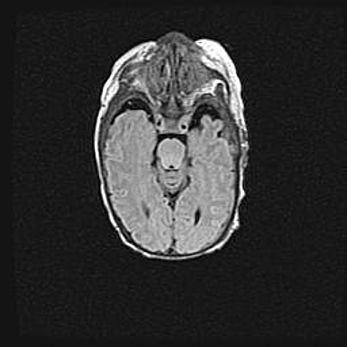

Мальформация Денди-Уокера. Киста задней черепной ямки.

Агенезия мозолистого тела.

Возраст: 2,5 месяца

Вес: 2420 г

Пол: женский

Окружность головы: 37 см

Срок гестации: 32 недели

Мальформация Денди—Уокера — редкий вид патологии ЦНС, представляющий собой врожденный порок развития каудального отдела ствола и червя мозжечка, ведущий к неполному раскрытию срединной (Мажанди) и латеральных (Лушка) апертур IV желудочка мозга. Для этогно синдрома характерна триада симптомов: гипотрофия червя мозжечка и/или полушарий мозжечка, кисты задней черепной ямки, гидроцефалия различной степени. В 70% случаев порок сочетается и с другими аномалиями головного мозга, в частности с агенезией мозолистого тела.